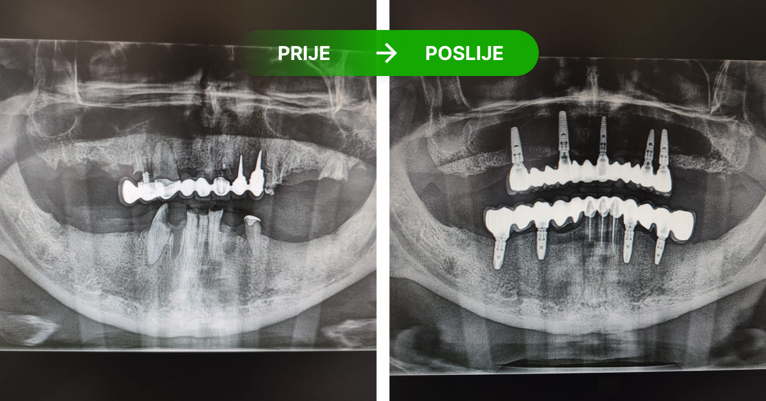

Protetika: prije i poslije. Foto: Dental Centar Jelić

Protetika na implantatima

Protetika u kojoj implantati imaju ulogu korjena zuba.

Na četiri ili šest implatanta izrađujemo keramičke mostove